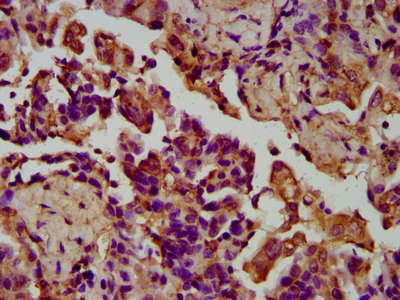

IHC image of CSB-PA818678LA01HU diluted at 1:200 and staining in paraffin-embedded human lung cancer performed on a Leica BondTM system. After dewaxing and hydration, antigen retrieval was mediated by high pressure in a citrate buffer (pH 6.0). Section was blocked with 10% normal goat serum 30min at RT. Then primary antibody (1% BSA) was incubated at 4°C overnight. The primary is detected by a biotinylated secondary antibody and visualized using an HRP conjugated SP system.

IHC image of CSB-PA818678LA01HU diluted at 1:200 and staining in paraffin-embedded human liver cancer performed on a Leica BondTM system. After dewaxing and hydration, antigen retrieval was mediated by high pressure in a citrate buffer (pH 6.0). Section was blocked with 10% normal goat serum 30min at RT. Then primary antibody (1% BSA) was incubated at 4°C overnight. The primary is detected by a biotinylated secondary antibody and visualized using an HRP conjugated SP system.